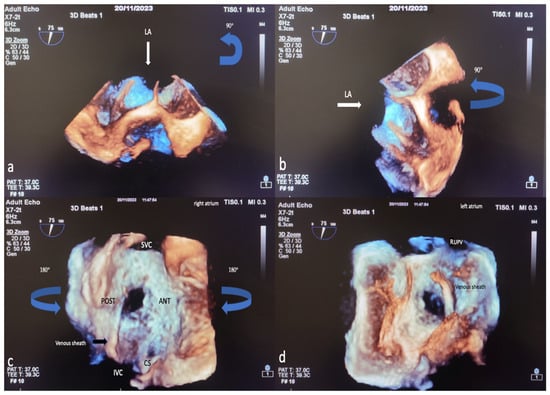

The TEE procedure was performed under local infiltration oropharyngeal anesthesia with lidocaine mucilage in patients who tolerated it. For patients who could not tolerate it, TEE was performed under sedation. All patients were fasted for 12 h before TEE. During the procedure, vital signs such as heart rate, blood pressure, electrocardiography (ECG), and fingertip blood oxygen saturation were monitored. All 2D TEE and 3D TEE imaging was performed using the Philips EPIQ7 Cardiac Ultrasound System and the X7-2t (Bothell, WA, USA, Ultrasound Transducer) TEE probe. The TEE procedure was performed according to the American Society of Echocardiography (AED)’s standard protocol [19]. Initially, ASD diameters, shapes, and morphologies were visually examined and measured with 2D TEE in the evaluation made from four-chamber (0°), short axis (30–60°), bicaval axis (90–120°) and 0–180° angles. Measurement of the minimum and maximum diameters of the ASD was obtained by routine angular and rotational (counterclock vise) movement of the 2D TEE probe between 0 and 180°. In 2D ASD imaging, the maximum and minimum diameters were measured and recorded when the defect sizes appeared largest at the end of the cardiac systolic phase. Images are routinely taken by the recommendations in the 3D echocardiography guide. A sufficient 3D TEE imaging dataset was collected by recording 3D full volume, Live 3D, 3D zoom, X plane (multiplane, biplane), and multiple-beat 3D imaging samples volume images accompanied by ECG [20]. The first image obtained when switching from a mid-esophageal bicaval examination in 2D TEE to 3D TEE zoom mode is shown in Figure 2a. The image in Figure 2b is obtained by rotating the first image 90 degrees counterclockwise. The images of RA and LA (en face), respectively, obtained by 3D TEE zoom mode imaging are shown in Figure 2c,d. The EAE/ASE recommendations for image acquisition and display using three-dimensional echocardiography practice guidelines are the basis for image acquisition, display, and image optimization. Generally, gain and compression settings were set in the midrange and optimized with slightly higher time gain controls (time gain compensation) to enable the greatest flexibility with postprocessing gain and compression [11]. Two experienced operators performed the TEE procedure, and two experienced interventional cardiologists performed ASD closure.

Figure 2.

Image of percutaneous ASD closure process with 3D TEE, image optimization in 3D TEE. In 2D TEE examination, when the bicaval window (when examining the SVC-IVC plane section at approximately 80–120 degrees) is switched to 3D zoom examination, the Image on the monitor is obtained with the transducer facing the left atrium perpendicularly from above (a). The operator first views the Image 90 degrees counterclockwise (blue arrow) (a) in the sagittal axis and then rotates 90 degrees to the left on the vertical axis (blue arrow) (b) to obtain the right atrial view (c). After obtaining the RA (en face) view in this way, the LA (en face) view will be obtained by rotating 180 degrees in the vertical axis to the right or left (d). Based on these LA and RA facial views, ASD morphology and the status of the rims are easily identified. LA, left atrium; ANT, anterior; SVC, superior vena cava; POST, posterior; IVC, inferior vena cava; CS, coronary sinus; RUPV, right upper pulmonary vein; 2D, two-dimensional; 3D, three-dimensional. (The images included in this article were taken from Erzurum City Hospital Cardiology Clinic Echocardiography laboratory).